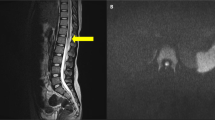

We report the case of a 1-month old, 28-week gestational age infant who presented with acute paraplegia after cardiopulmonary arrest. Later imaging confirms cerebral sinovenous thrombosis (CSVT) and a suspected infarction in the conus medullaris of the spinal cord. A prothrombotic state may explain the numerous areas of infarction visualized on neuroimaging. To our knowledge this is the first case report of acute and persistent paraplegia in an infant with CSVT and conus medullaris injury, which may be due to venous infarction of the spinal cord.